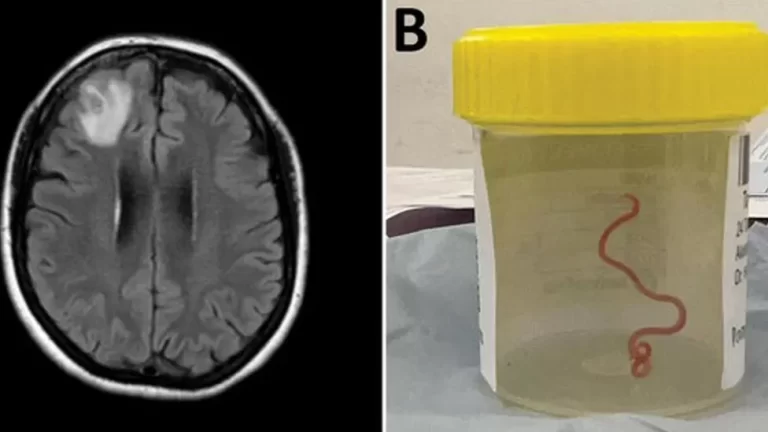

In a world first, scientists say that an 8cm worm has been found alive in the brain of an Australian woman.

The “string-like structure” was pulled from the England-born patient's damaged frontal lobe tissue during surgery in Canberra last year.

The red parasite could have been there for up to two months. Researchers are warning that the case highlights the increased danger of diseases and infections being passed from animals to people.

“Everyone [in] that operating theatre got the shock of their life when [the surgeon] took some forceps to pick up an abnormality and the abnormality turned out to be a wriggling, live 8cm light red worm,” said Sanjaya Senanayake, an infectious diseases doctor at Canberra Hospital.